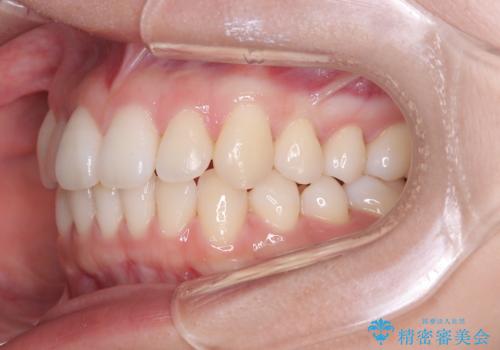

非抜歯矯正で八重歯を改善|短期間8か月で美しい歯並びに|インビザラインライト上顎のみで矯正

- 「八重歯を治したい」との主訴でご来院された患者様です。。

非抜歯で上顎のみインビザラインライトを使用して矯正を行いました。

短期間(約8か月)の治療で歯並びが整い、患者様も大変喜ばれました。